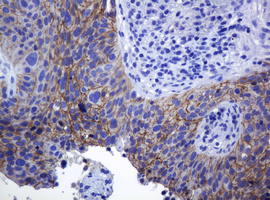

Immunohistochemical staining of paraffin-embedded Carcinoma of Human prostate tissue using anti-CDH1 mouse monoclonal antibody. (Heat-induced epitope retrieval by 10mM citric buffer, pH6.0, 120°C for 3min, M00063-5)